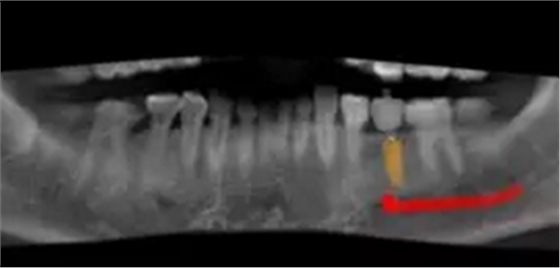

术前,导板设计工程师,根据CBCT以及模型数据,将患者的解剖结构、软组织形态和修复效果数字化三维重建,在设计软件内进行虚拟修复体冠设计,同时与临床医生一起,根据#35牙槽骨高度以及宽度,结合下牙槽神经管,设计好合适的种植位点。

根据上述植入和修复方案,立体设计Implant Guide™全程导板,鉴于下颌需避让下颌神经管,并考虑到种植体与颊舌侧、近远中侧的关系,设计在该牙位植入1颗Alpha-Bio Tec ICE 4.2x 10mm的植体。

术前术后CBCT数据对比分析,植体就位准确。